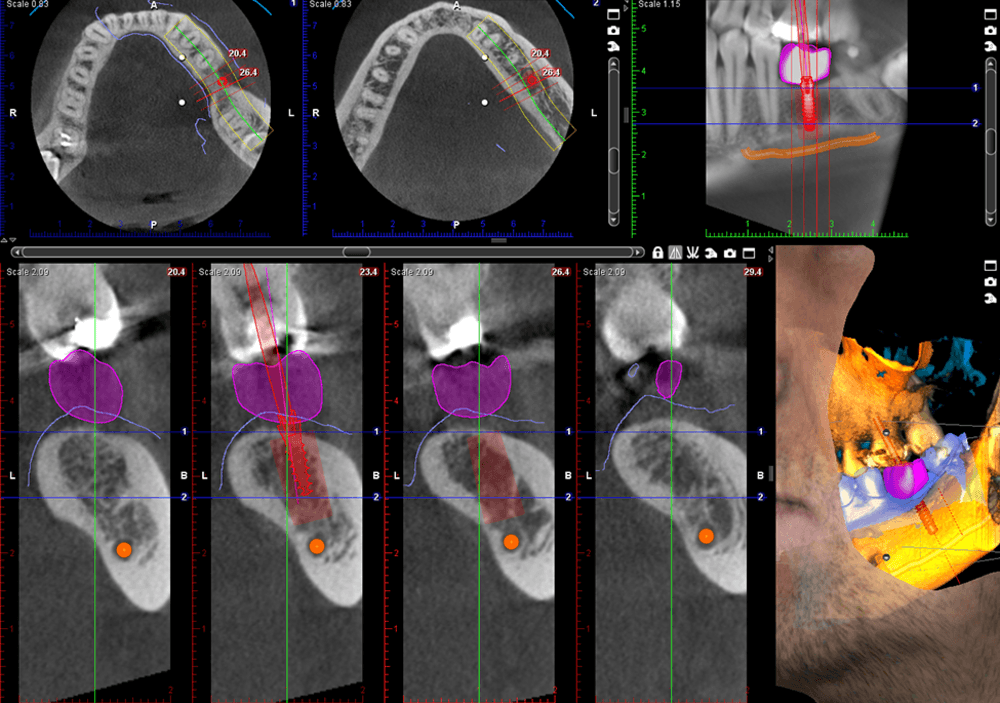

Planmeca ProMax® 3D

Meet the Planmeca ProMax® 3D imaging family, a comprehensive suite of solutions tailored to meet the unique demands of dental practices. With unparalleled image quality and cutting-edge technology, these systems provide practitioners with the versatility and precision needed for accurate diagnostics and treatment planning.

Discover the Planmeca ProMax® 3D family, meticulously designed to meet the needs of every dental practice. Known for its unparalleled image quality, each system reflects Planmeca's commitment to excellence. Equipped with noise reduction technology, these units deliver unmatched image clarity. Enjoy True Extraoral bitewings, segmented pans, and AutoFocus for crystal clear pan images every time. Available features like Planmeca Ultra Low Dose™ and Planmeca CALM® for patient safety